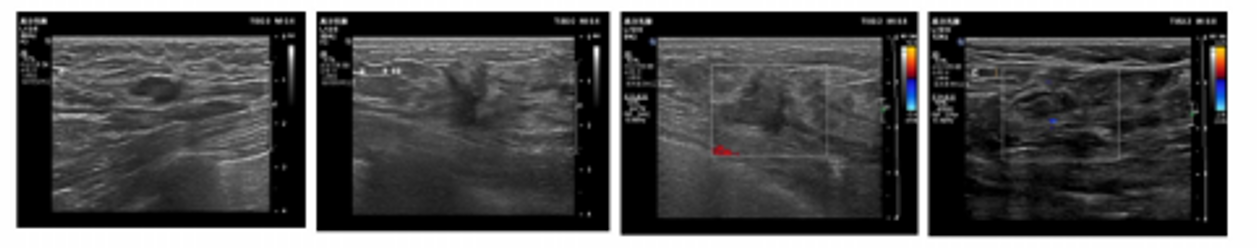

现病史:患者2021-9-13因“发现左乳肿瘤2月余”于我院门诊就诊,行乳腺彩超示:左侧乳腺9-10点可见一1.4*1.2cm大小实质性低回声团块(BI-RADS 5类)建议彩超引导下穿刺。左侧腋下内可见数个实质性低回声光团,境界清晰,内回声均匀,最大约1.5*0.7cm,建议彩超引导下细针穿刺。遂行乳腺和淋巴结穿刺活检。

超声检查:双侧乳腺组织未见明显增厚,回声分布均匀,CDFI示未见异常血流信号,左侧乳9-10点可见一1.4x1.2cm大小实质性低回声团块,境界欠清晰,无包膜,内回声不均匀,周边可见伪足样伸展,后方回声衰减。CDFI示其内未见血流信号。双侧腋下探查:双侧腋下内可见数个实质性低回声光团,境界清晰,内回声均匀,左侧最大约1.5x0.7cm,右侧最大约1.4x0.6cm,左侧较大淋巴结局部皮质增厚。CDFI示可见血流信号。

由于患者为三阳性乳腺癌,且伴有腋窝淋巴结转移,未见远处转移,因此推荐接受新辅助治疗,治疗方案为TCbHP。第3次和第5次新辅助治疗后,超声检查提示,左乳9-10点未见异常团块,双侧乳腺组织未见明显增厚,回声分布均匀,CDFI示未见异常血流信号。双侧腋下未见异常实质性光团,CDFI示血流信号未见异常。